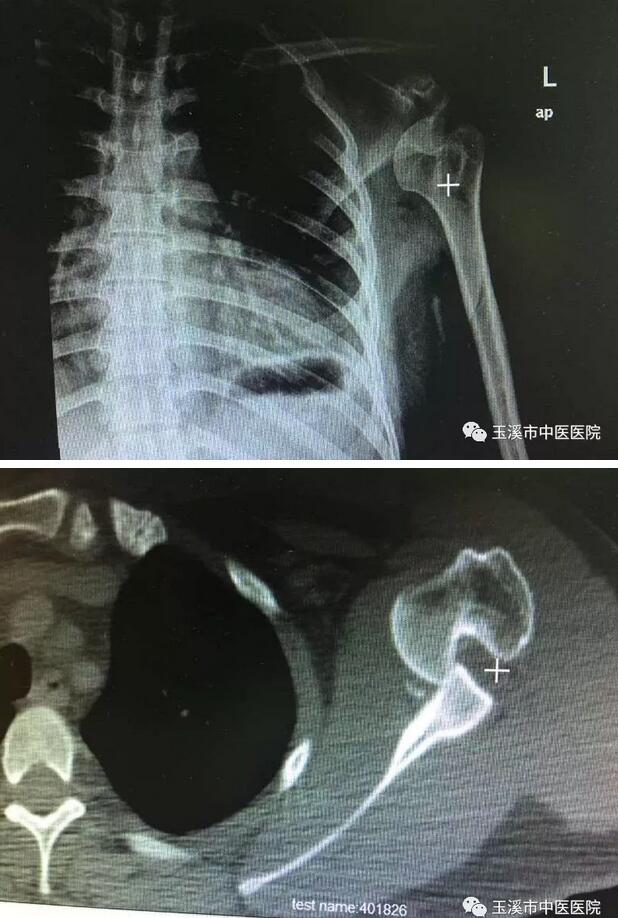

玉溪市中醫(yī)醫(yī)院骨傷一科創(chuàng)新手法整復(fù)肩關(guān)節(jié)脫位

近年來(lái),我院骨傷一科潛心研究古今中外的各種肩關(guān)節(jié)脫位整復(fù)方法,綜合各方優(yōu)勢(shì),創(chuàng)造性地設(shè)計(jì)出“牽腕蹬肩法”治療肩關(guān)節(jié)脫位,并在實(shí)踐中不斷完善,取得極好療效。

研究成果《“牽腕蹬肩”法治療盂下型肩關(guān)節(jié)脫位38例體會(huì)》發(fā)表在中國(guó)科技核心期刊《中國(guó)中醫(yī)骨傷科雜志》第23卷第7期,另一篇《“牽腕蹬肩”法對(duì)比“手牽足蹬”法治療肩關(guān)節(jié)前脫位體會(huì)》也被國(guó)家級(jí)期刊《光明中醫(yī)》錄用。

肩關(guān)節(jié)脫位是一種常見(jiàn)疾病,約占全身關(guān)節(jié)脫位的40%以上。肩關(guān)節(jié)脫位的復(fù)位方法非常之多,諸如《普濟(jì)方·折傷門(mén)》之“拔伸足蹬法”后世又稱(chēng)之為“手牽足蹬法”、唐·藺道人《仙授理傷續(xù)斷秘方》之“椅背復(fù)位法”、清·胡廷光《傷科匯纂》之“拔伸拖入法”、“膝頂推拉法”、“上舉內(nèi)收旋轉(zhuǎn)患肢復(fù)位法”、“零度位法”、“上舉牽引回旋法”等。“手牽足蹬”法是最為普遍使用的復(fù)位方法。但以上方法各有偏頗,無(wú)法對(duì)所有脫位進(jìn)行理想整復(fù)。

“牽腕蹬肩”法是利用雙手握住患肢腕部,反側(cè)足蹬于患側(cè)肩上作135°順勢(shì)牽拉,此時(shí)肩周肌群和關(guān)節(jié)囊裂口松弛。此法不需要麻醉,患者無(wú)痛苦感,醫(yī)生單人以很小的作用力就能達(dá)到復(fù)位。近年來(lái),骨傷一科的“牽腕蹬肩”治療肩關(guān)節(jié)脫位166例全部一次成功,無(wú)神經(jīng)損傷、骨折等并發(fā)癥,相對(duì)傳統(tǒng)方法優(yōu)勢(shì)明顯。 對(duì)高齡骨質(zhì)疏松兼有胸肋損傷者尤其適用,開(kāi)創(chuàng)了肩關(guān)節(jié)脫位手法整復(fù)新局面,不愧為整復(fù)肩關(guān)節(jié)脫位的一種好方法。